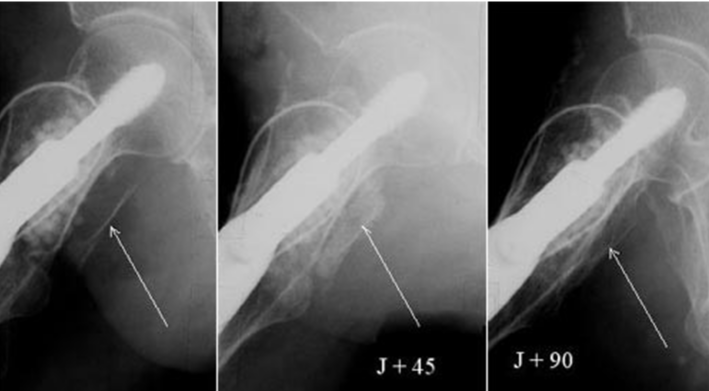

X-Rays below show the gradual disappearance of natural coral on a visual scale (Figure 2D-F).

The posterior plate is broken in one big fragment. 90 days after it is anatomically in place (Figure 12).

Figure 12: The posterior plate is broken in one big fragment. 90 days after it is anatomically in place.